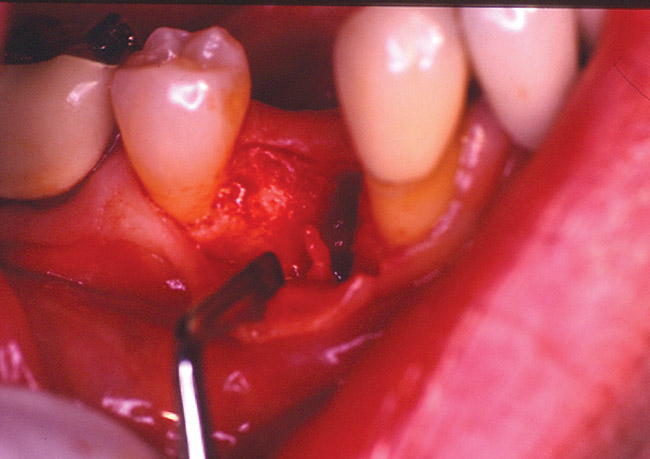

Figure 2b  After extraction of the tooth, the socket was curetted. It was noted that there was bone loss on the buccal aspect because of the presence of infected tissue.

Figure 2b

Figure 2c  The socket was grafted using a combination of freeze-dried bone allograft and a calcium sulfate bone graft barrier.

Figure 2c

The patient was scheduled for extraction of the tooth, along with socket preservation. After extraction, the socket was curetted. Bone loss on the buccal aspect as a result of infected tissue was noted (Figure 2B). After socket curettage, the socket was grafted using a combination of freeze-dried bone allograft combined with a calcium sulfate bone graft barrier (Figure 2C). The patient was placed on antibiotic and anti-inflammatory medications. Six months after the socket preservation procedure, the site was prepared for implant placement. At the time of implant placement, a core of bone was harvested from the socket preservation site and analyzed histologically (Figure 2D and Figure 2E).